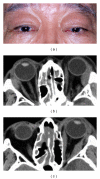

Orbital IgG4-related disease, which can occur in adults of any age, is characterized by IgG4-positive lymphoplasmacytic infiltrations in ocular adnexal tissues. The signs and symptoms include chronic noninflammatory lid swelling and proptosis. Patients often have a history of allergic disease and elevated serum levels of IgG4 and IgE as well as hypergammaglobulinemia. Orbital IgG4-related disease must be differentiated from idiopathic orbital inflammation and ocular adnexal marginal zone B-cell lymphoma to ensure appropriate and effective treatment. Systemic steroid therapy decreases the size of the lesions, but relapse often occurs when systemic steroid therapy is discontinued.